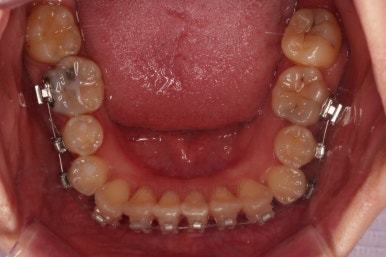

치열은 매우 가지런해졌고요.

추후에 발치 공간을 모아나가야 합니다.

윗니 앞니는 급한대로 신경치료 부터 진행했고, 최종 심미보철은 교정 후 미루었습니다.

공간을 줄여나가고 순차적으로 충치치료도 마무리 해갑니다.